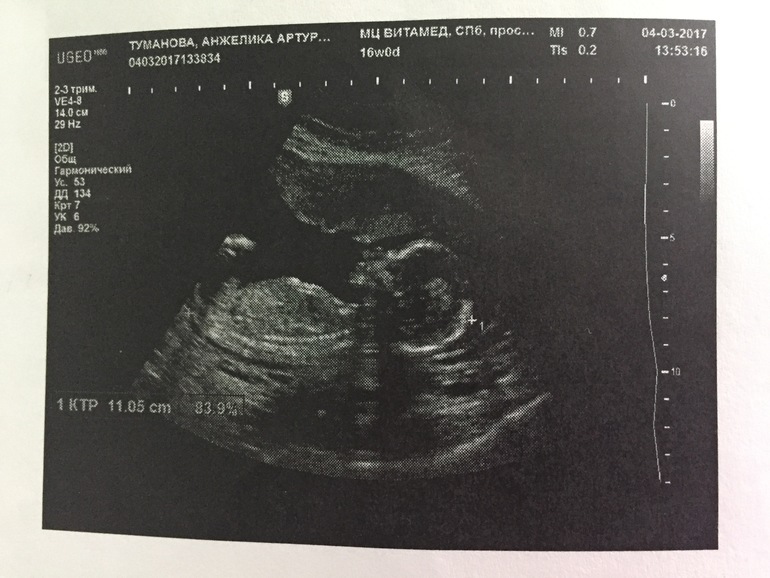

По результатам:

на 4 марта было 16 недель и 1 день.

Вес плода 145 грамм.

КТР - копчико-теменной размер плода 11,05 см.